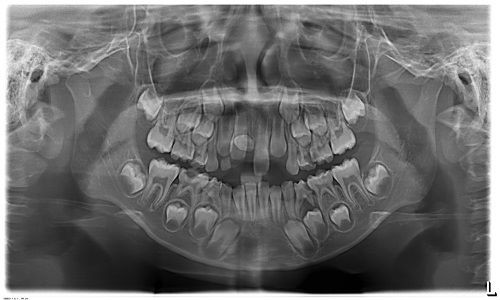

Tới viện cháu P được chụp phim, các bác sỹ phát hiện bé trai bị rối loạn mọc răng vĩnh viễn do răng thừa ngầm hàm trên.

Đánh giá vị trí răng ngầm bất thường, cản trở việc mọc răng cửa vĩnh viễn, bé được tư vấn nhập viện Răng Hàm Mặt Trung ương để phẫu thuật bỏ răng thừa ngầm.

| Hình ảnh răng mọc thừa (BV). |

Răng mọc thừa ngầm chỉ được phát hiện khi thăm khám nha khoa và qua các kỹ thuật kiểm tra như chụp X-quang, chụp CT Conebeam. Chính vì vậy, việc thăm khám định kỳ răng miệng là cần thiết.